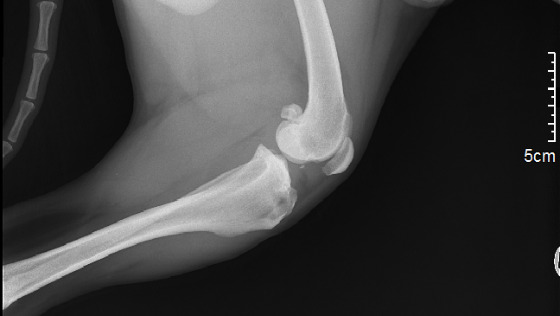

Desmo ma przerwane więzadło krzyżowe przednie w tylnej lewej łapie. Obecnie w ogóle na niej nie staje.

Wizyta u weterynarza wskazała na luźność stawu kolanowego - przerwanie więzadła krzyżowego w stawie kolanowym i zmiany zwyrodnieniowe stawu. Uraz wystąpił wskutek wrodzonej wady stawów kolanowych, kwestia czasu aż w drugiej łapce stanie się to samo.